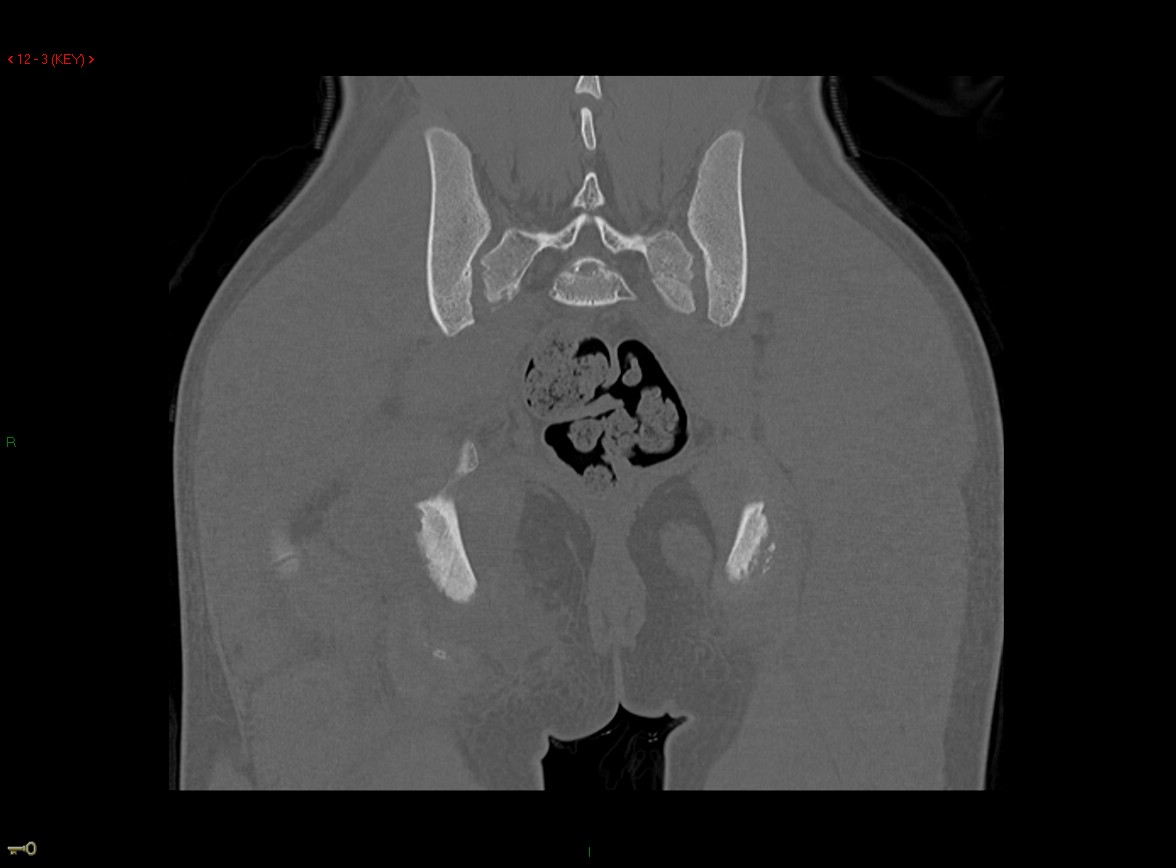

Figure 4 for case Ischial tuberosity ( RID2550 ) avulsion

Figure 4